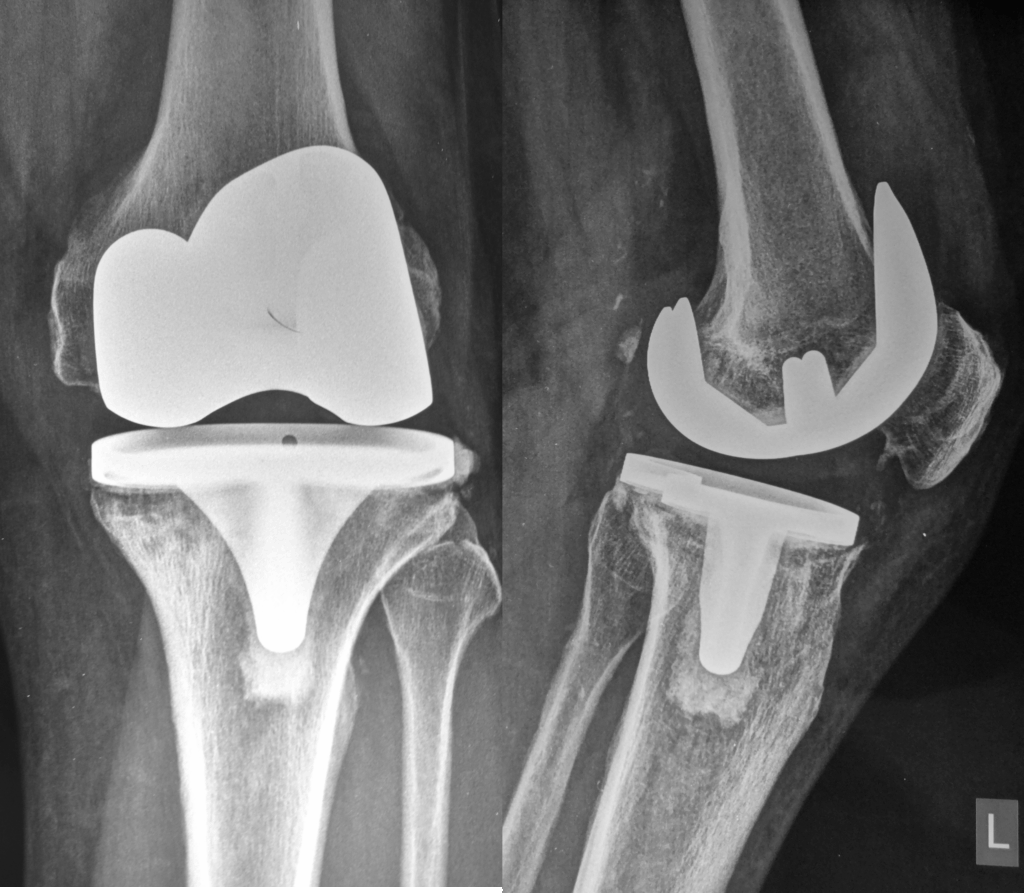

Μηχανική αστοχία υλικών (π.χ. σπάσιμο, φθορά πολυαιθυλενίου)

Αφαίρεση της παλιάς πρόθεσης

Τοποθέτηση νέας πρόθεσης, ειδικά σχεδιασμένης για αναθεωρήσεις

Οι προθέσεις αναθεώρησης είναι πιο σταθερές, μακρύτερες και συχνά συνδυάζονται με μοσχεύματα ή μεταλλικά ενθέματα.